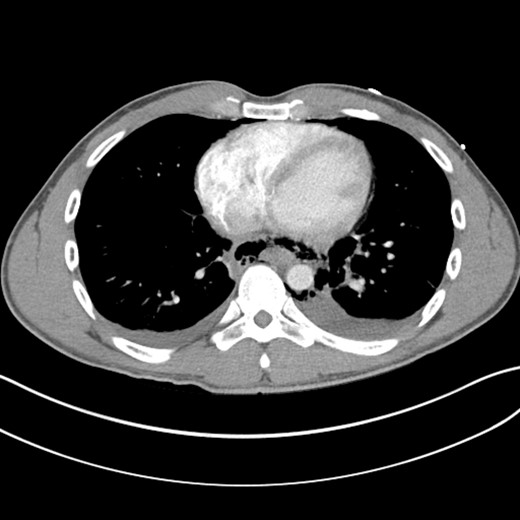

A computed tomographic scan revealed air and fluid surrounding the esophagus (Fig. 1). Esophagogram performed with water-soluble contrast media showed a distal esophageal perforation with a free leak into a large mediastinal cavity to the left of the esophagus (Fig. 2). The patient was triaged directly to the operation room. A left chest tube was placed with improvement in his oxygenation, and grossly murky fluid was drained. Esophagogastroduodenoscopy (EGD) was performed next and revealed a very small caliber esophagus with concentric ringed appearance. A tight stricture was noted in the mid-esophagus, which only allowed passage of a pediatric gastroscope. In the lower esophagus, a 2-cm tear with necrotic edges was visualized 3 cm above the gastroesophageal (GE) junction. With this diffusely strictured and very diseased appearance of the esophagus, the decision was made to proceed with stent placement and thoracoscopic drainage of the mediastinum rather than primary surgical repair via thoracotomy. A fully covered, 15 cm × 19 mm, EndoMAXX® esophageal stent was successfully placed covering the perforation site. Mediastinal washout and drainage was performed subsequently via left thoracoscopy. A postoperative esophagram showed no leak and the patient was started on a liquid diet that was tolerated well. His hospital stay was uneventful, and he was discharged on twice daily high-dose proton pump inhibitor (PPI) on post-operative Day 5. He was placed on a mechanical soft diet on discharge. Repeat upper GI study with water soluble contrast postoperatively showed no evidence extravasation. (Fig. 3)

Shows evidence of esophageal rupture and leak with pneumomediastinum and air and fluid surrounding the esophagus.